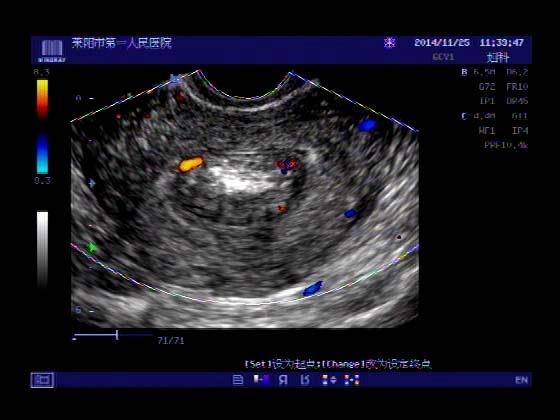

超声入门贴379---------粘膜下肌瘤(阴超的魅力)

女,43岁,月经量多3个多月,加重一个月

外院彩超检查提示:子宫后肌壁略高回声团------肌瘤?息肉?,盆腔少量积液

今天来我院检查:

巧妇难为无米之炊,经腹部超声确实很难定,阴超一目了然,乡镇医院诊断水平的提高更迫切的需要高档仪器的引进!